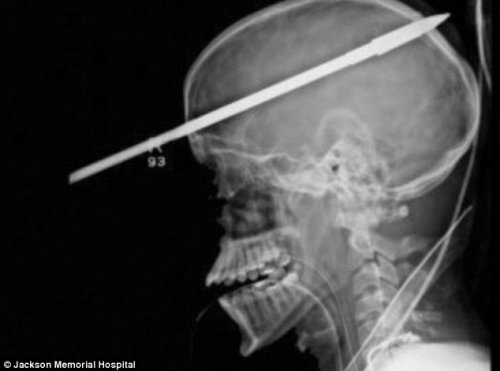

- 美国男孩被鱼叉戳穿脑颅 奇迹般存活 仍能说话(图)

- 时间:2012-06-21 10:36:31